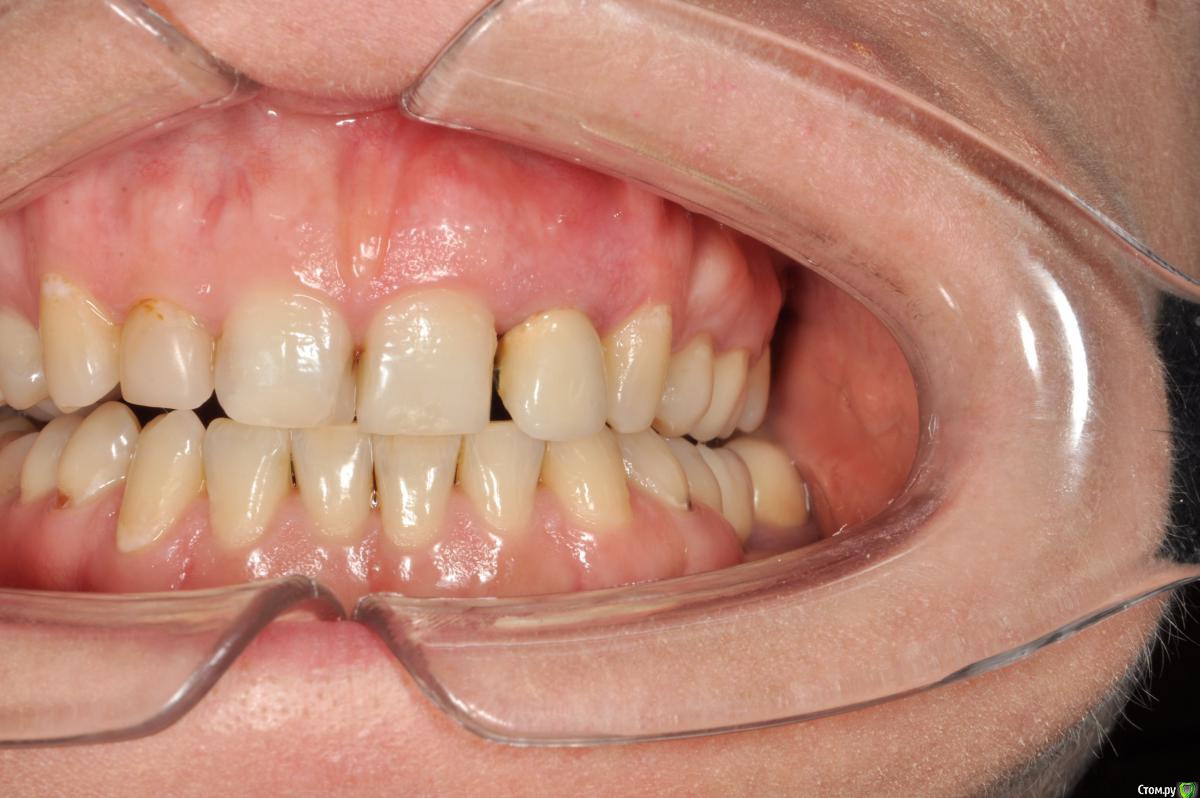

Пациентка 37 лет, не курит, соматически здорова. Частое выпадение ЛШКВ с коронкой. Диагностирована  фрактура вестибулярной стенки кореня зуба 22. Линия улыбки высокая. Биотип толстый.  Отсутствие вестибулярной пластинки, карман 8мм без ексудата.  Латеротрузия через 22.